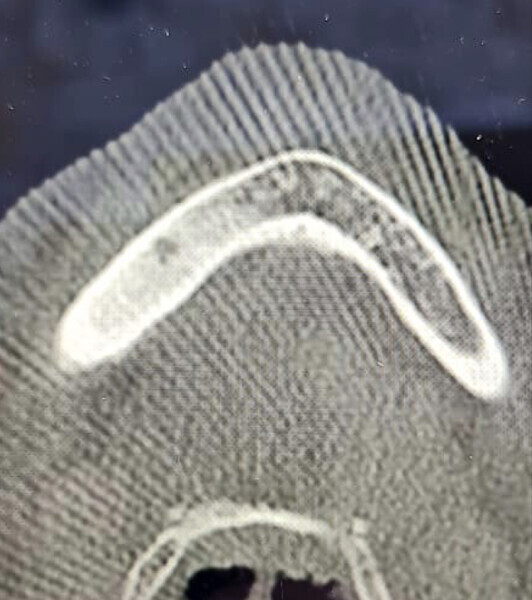

Fig. 8: Axial view of the CBCT scan showing a small apical infection of the mandibular right first molar, surrounded by an area of dense ossification extending over a large part of her mandible.

Figs. 11a–e: Axial and coronal views of the CBCT scan showing the quality of the bone in this typical bisphosphonate-associated bone necrosis case.